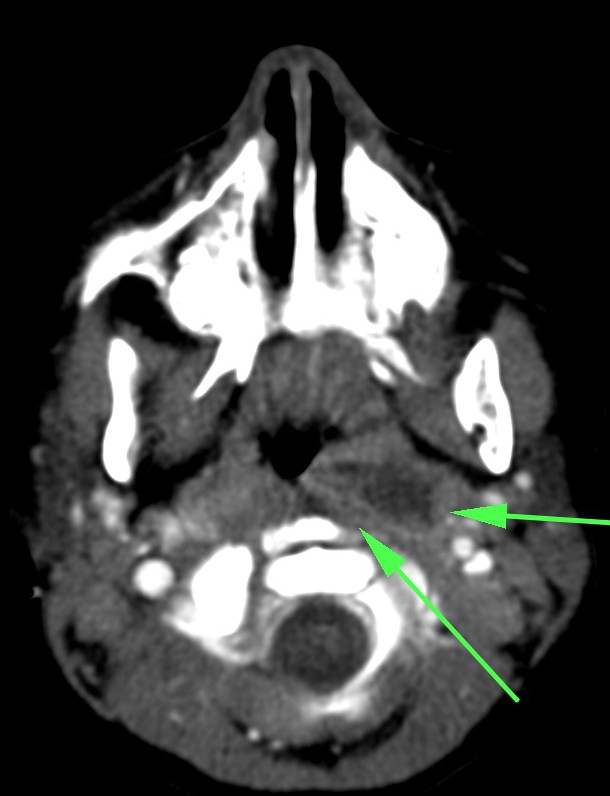

Síndrome de Lemierre: Tras una infección de la orofaringe, se produce tromboflebitis de vasos de cuello. Suelen ser infecciones asociadas con comobilidades tales como cirugía o radioterapia.

- Los defectos de repleción en la TC con contraste indican trombosis.

- La afectación de la grasa perivascular indica proceso inflamatorio.

- Si hay afectación de la vena yugular interna, existe alto riesgo de migración de émbolos sépticos a los pulmones. Por tanto, dada la gravedad, es fundamental realizar además una TC de tórax y es el radiólogo el que debe sugerir o establecer el diagnóstico de la enfermedad en un primer momento.